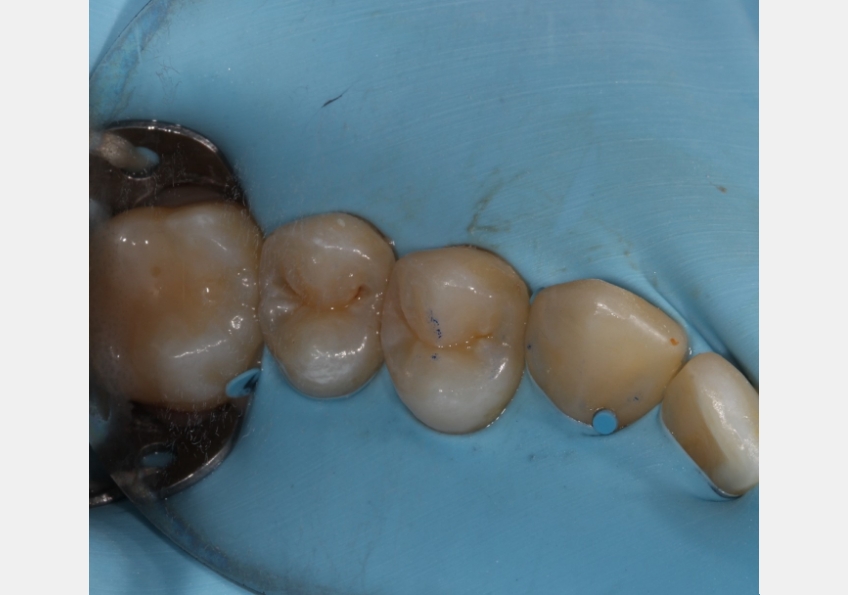

Use case #2: Class II composite restorations

Problem: Sectional matrix systems, although designed to provide optimal contour and interproximal contact for Class II composite restorations, can still result in flash and overhangs, particularly when dealing with rotated or mispositioned teeth.

Solution: In cases where a space between the ring and the matrix band is a concern, employing approximately 1 inch of Teflon tape on both the buccal and lingual aspects of the band ensures a closer, more intimate fit between the matrix band and the tooth. This approach significantly reduces the risk of flash and overhangs, ultimately producing a superior contour for the Class II restoration.